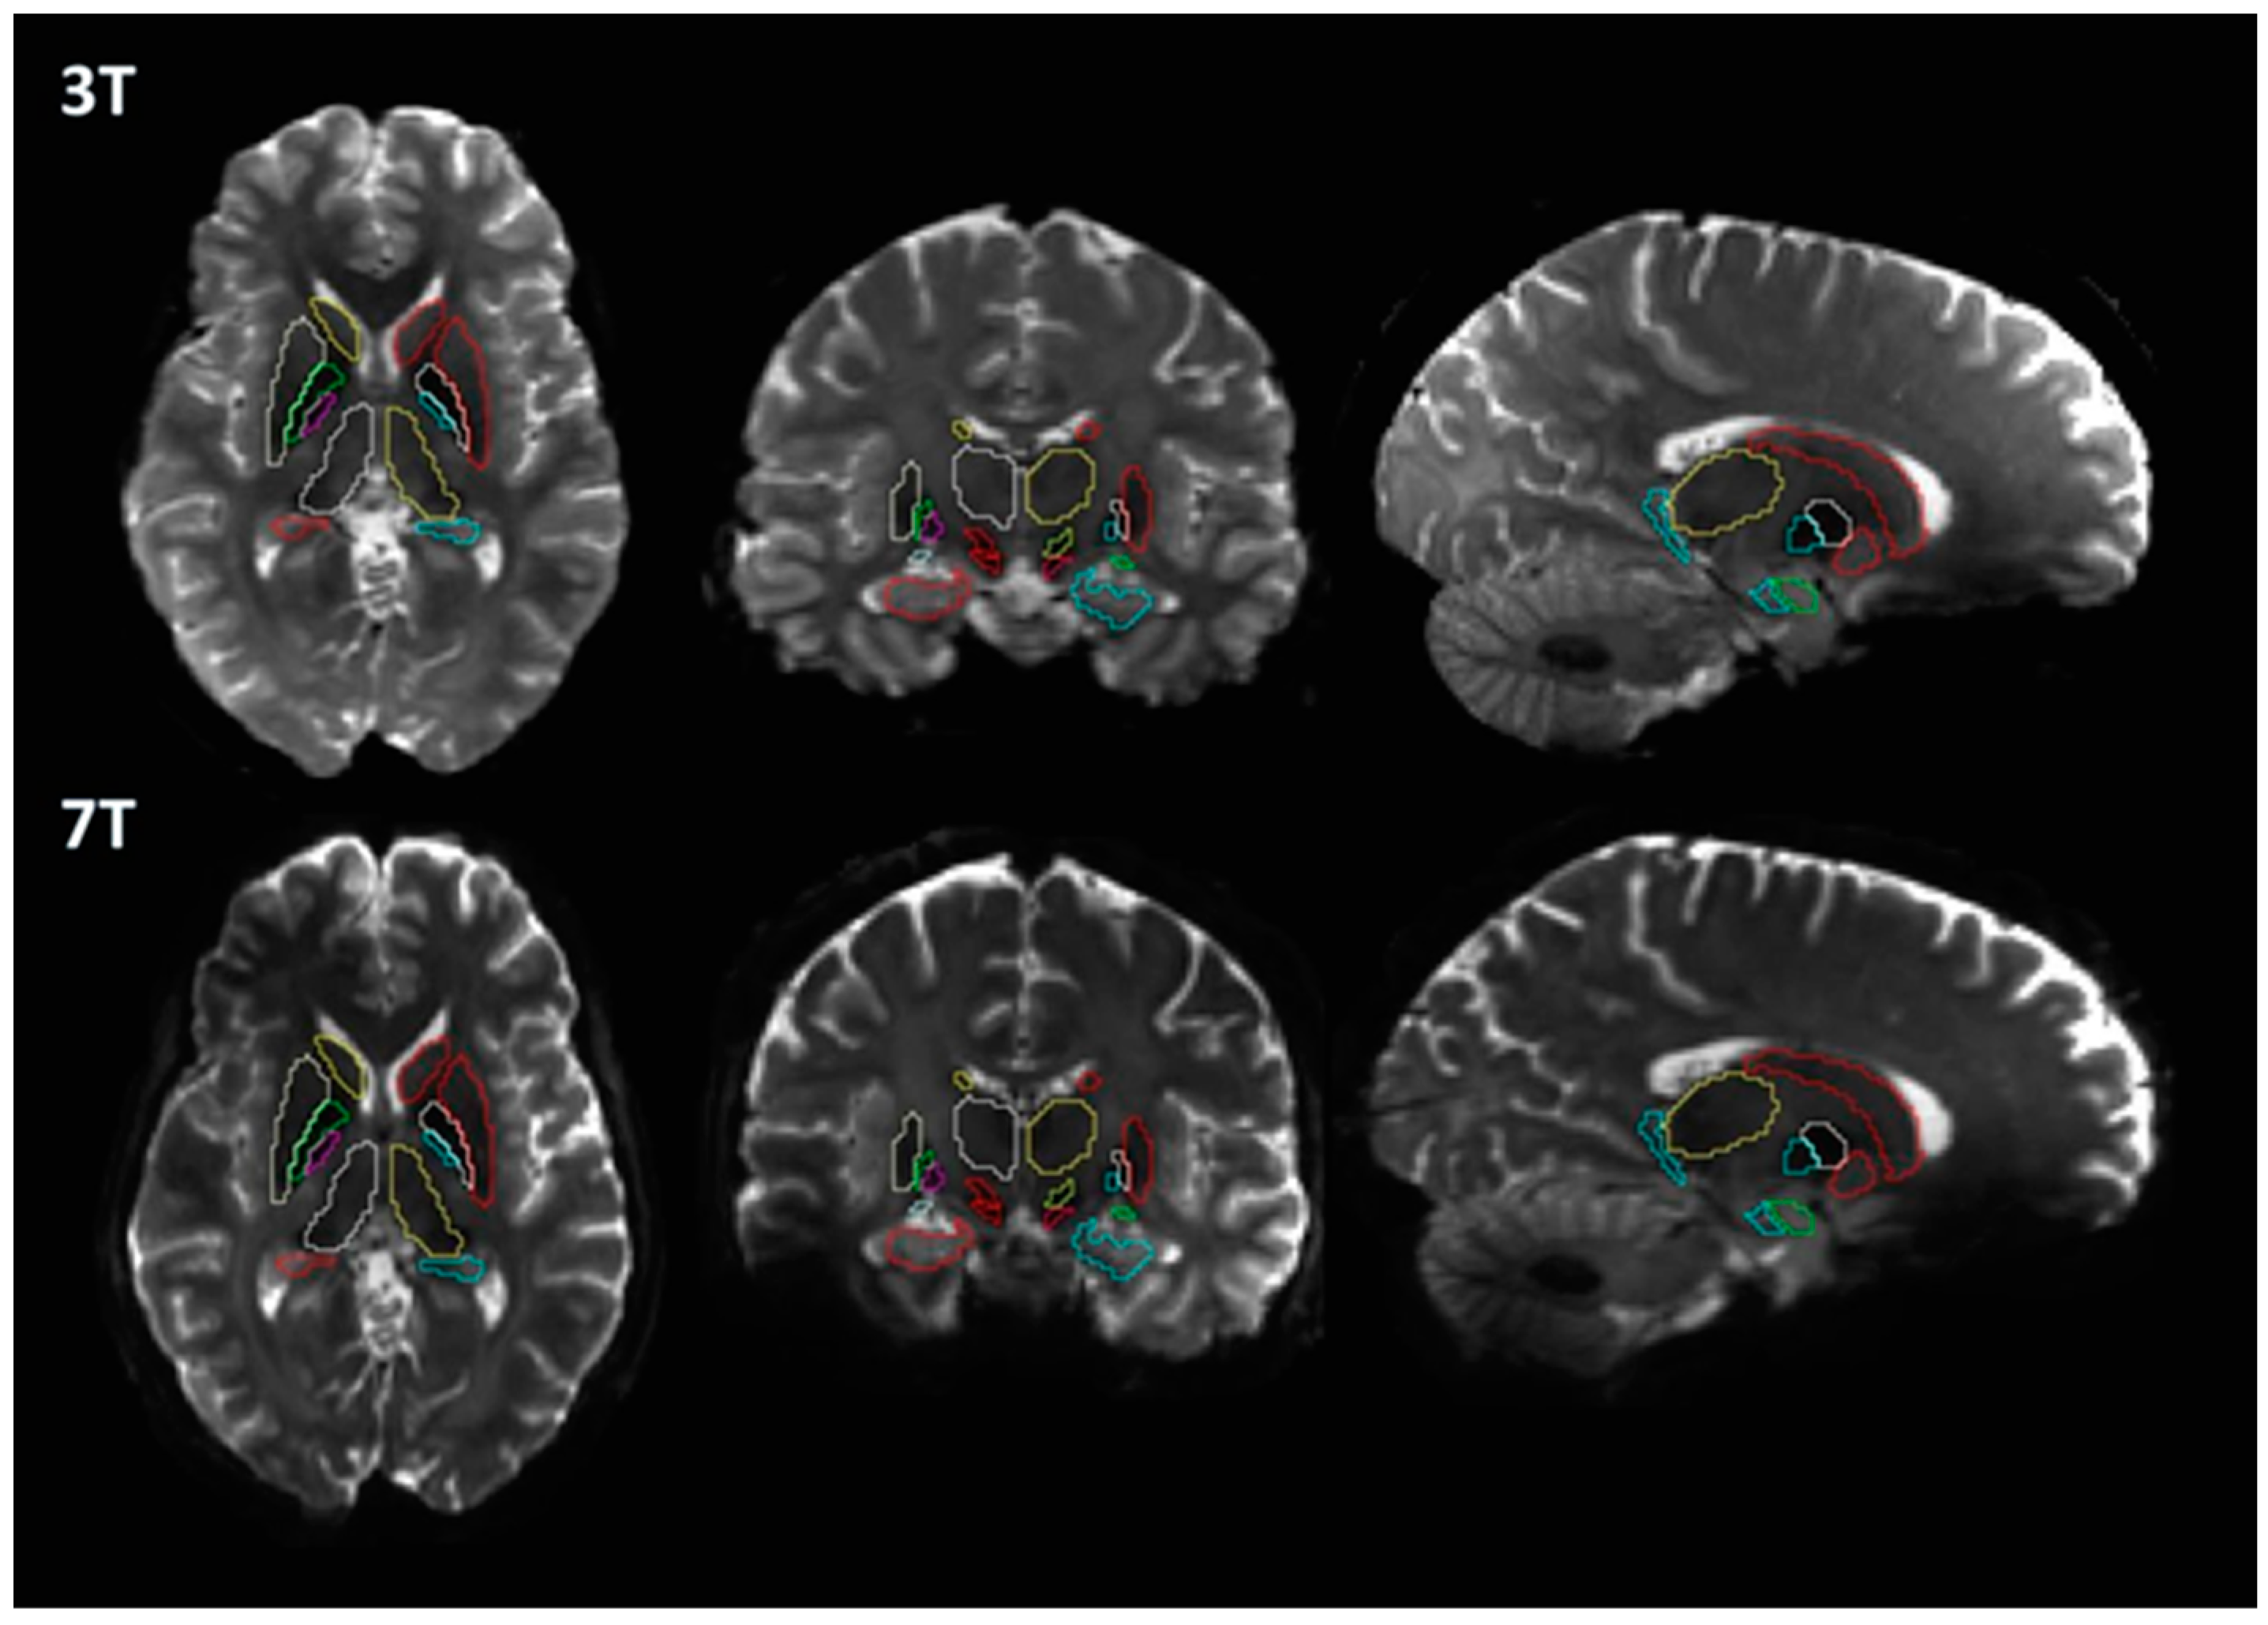

2.3. Image Processing

3. Results